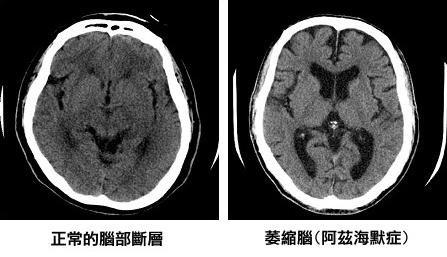

現在想想,那時爸爸的失智症已發展到中、重度,只是之前我們一直沒發現,他生病了…